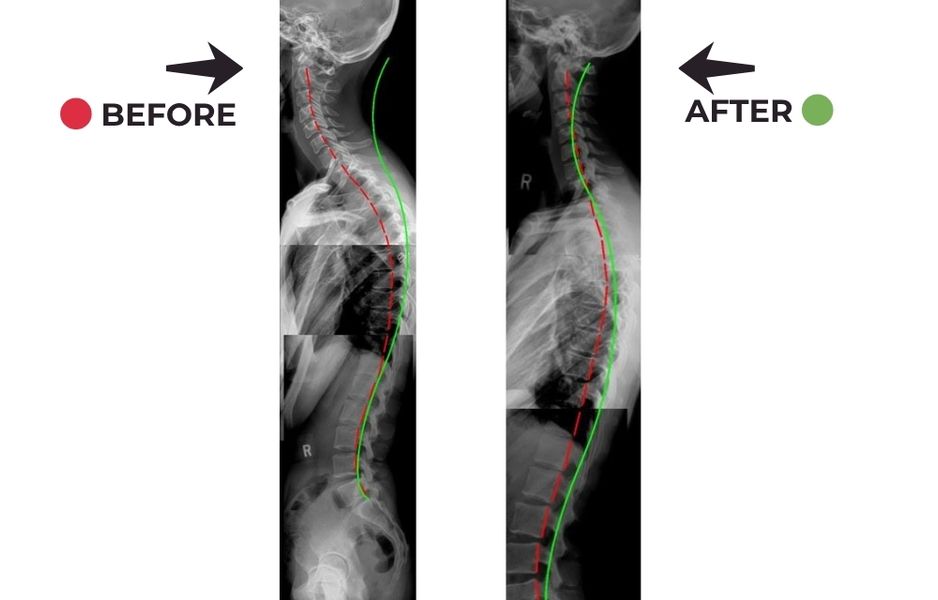

Yes. Chiropractors specialize in treating whiplash injuries by improving spinal alignment, reducing inflammation, and restoring normal movement.